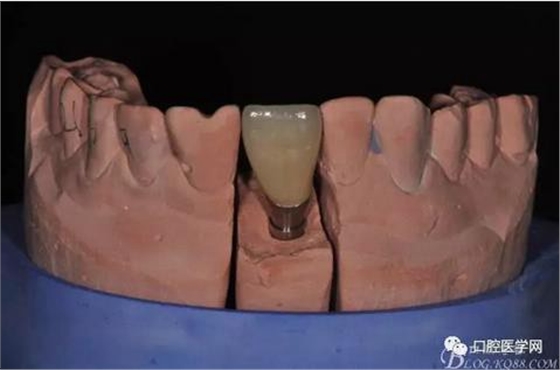

圖14 烤瓷冠模型唇側照

圖15 烤瓷冠模型舌側照